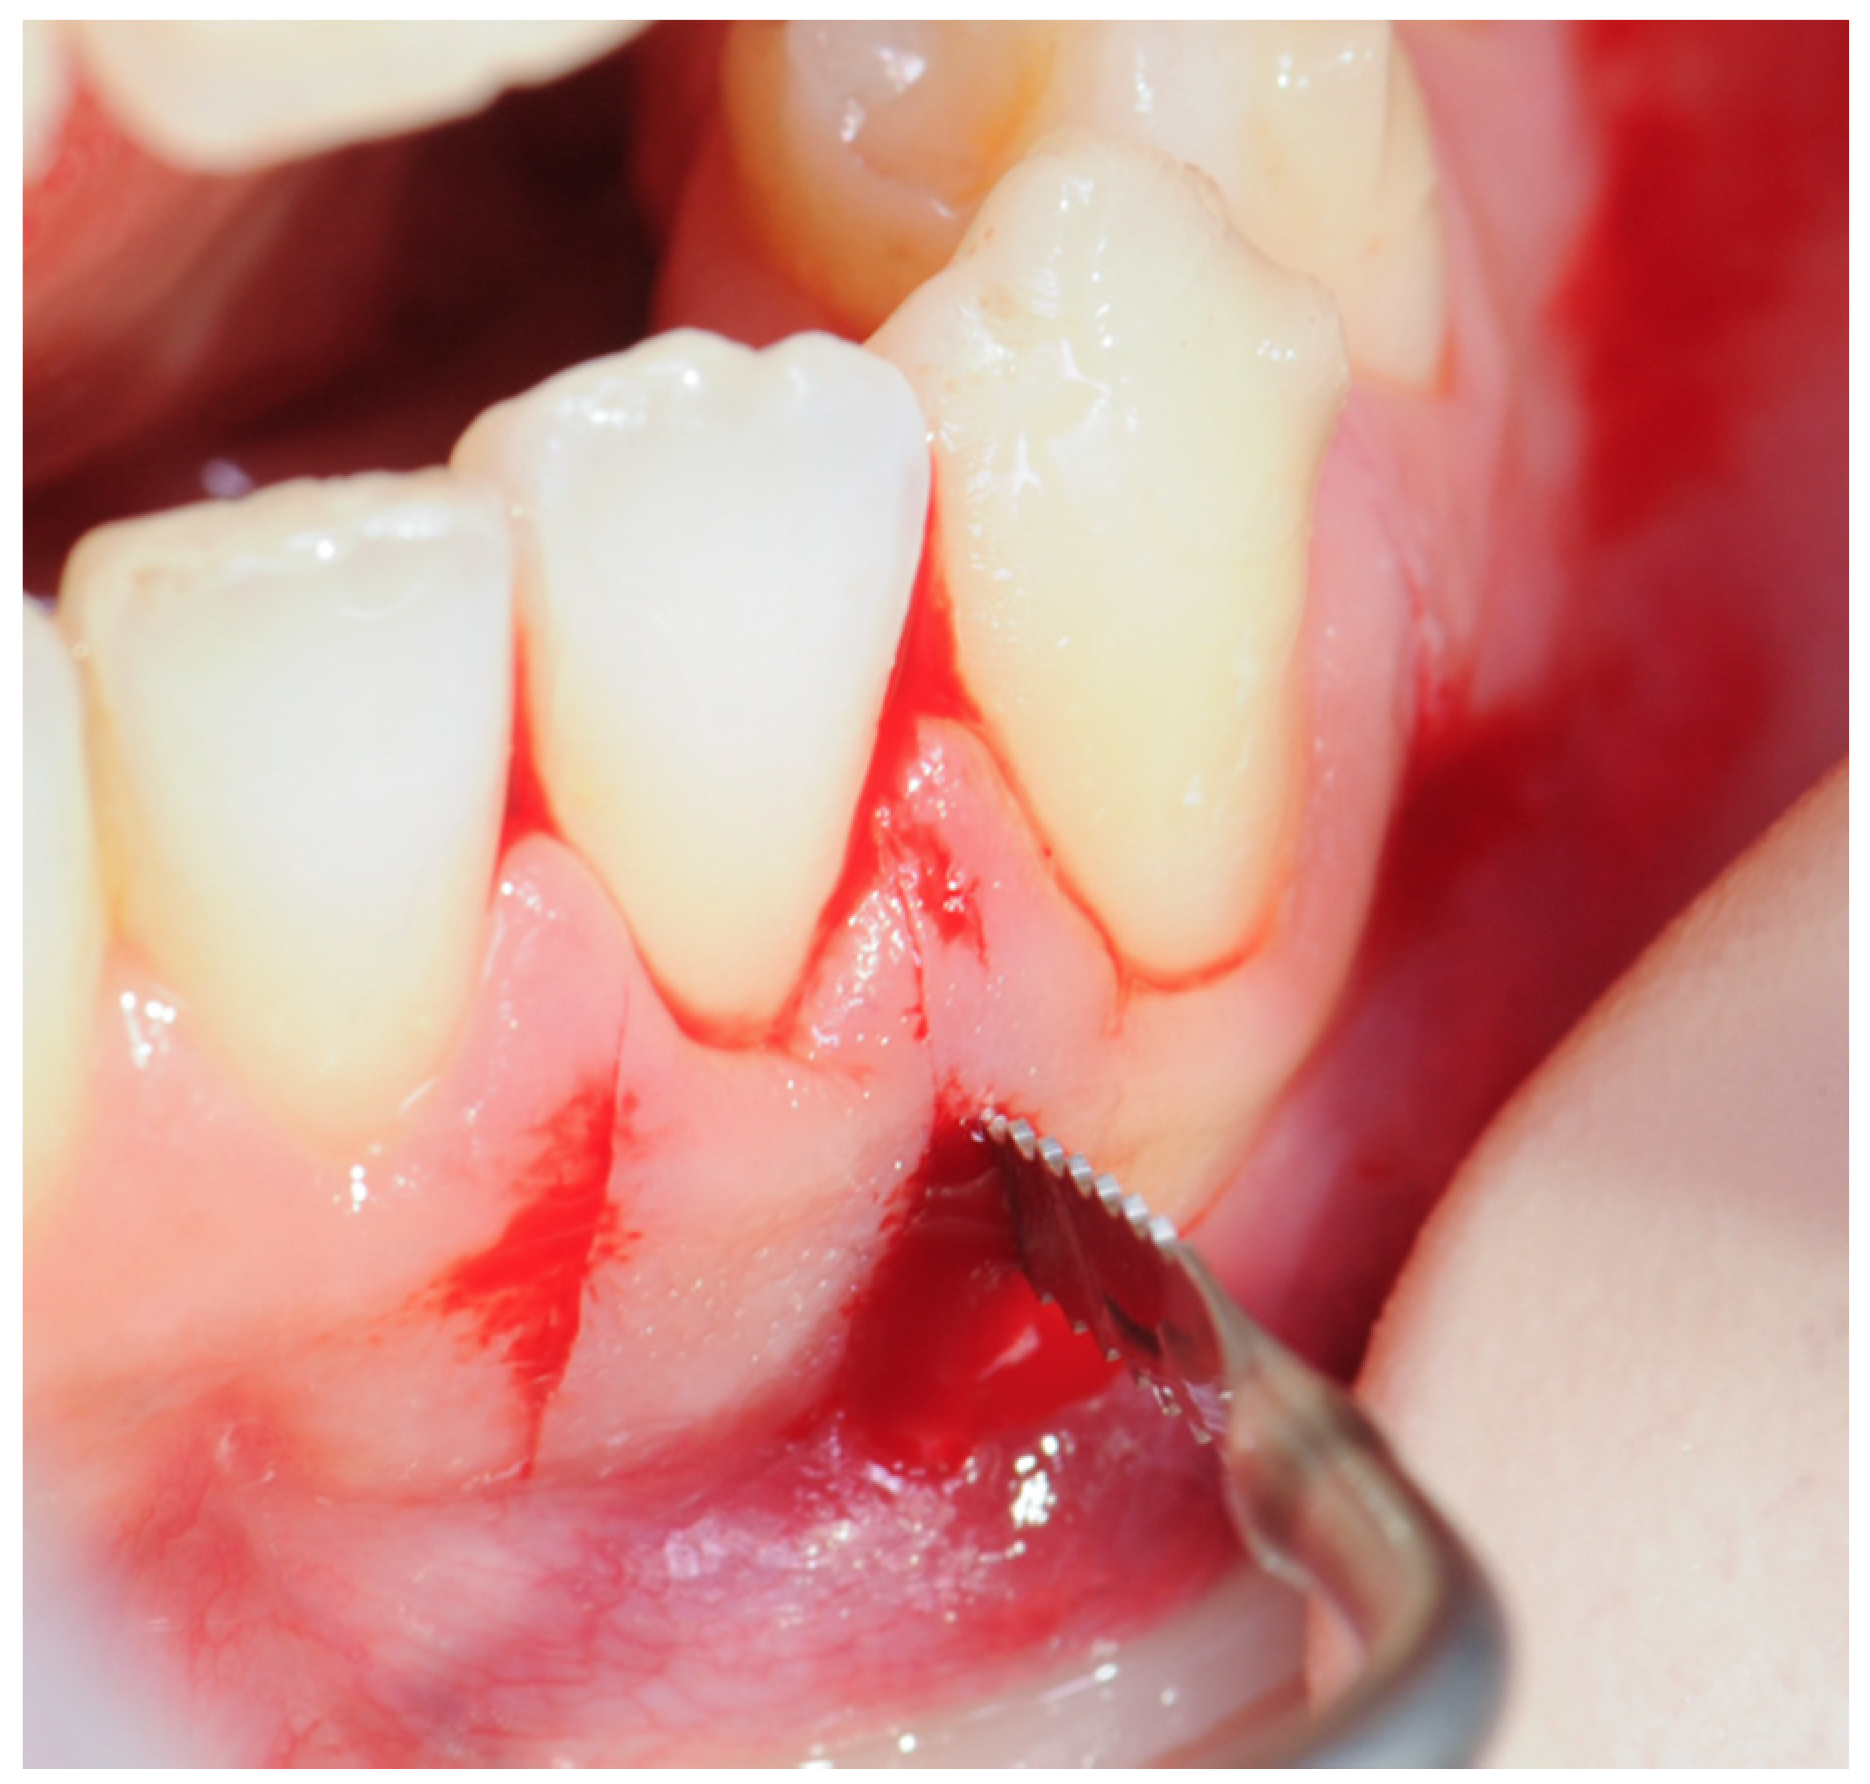

2.3. Surgical Procedure

2.3.2. Example 2—Extraction Space Closure